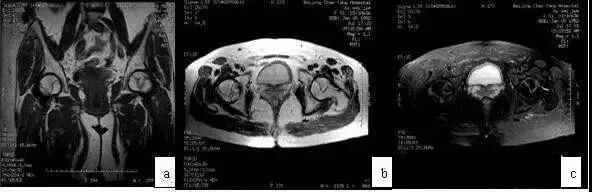

发生在髋关节的PVNS较膝关节少得多,患者多为青少年,常为单发,髋部中、轻度疼痛伴明显关节功能障碍,X线摄片可见股骨头、颈及髋臼皮质骨侵袭,囊性变,关节间隙变窄,此与ONFH不同,后者早、中期时关节间隙不变窄。

应用MRI检查,则鉴别不难。MRI示广泛滑膜病变(T1WI、T2WI均为低信号),病变侵犯广泛(股骨头颈、髋臼)是其特点,CT扫描可见骨皮质侵蚀,累及髋臼和股骨头、颈部,与ONFH鉴别不难(图10)。

图10 男,28岁,右髋钝痛二年,关节活动明显受限,诊断为色素沉着绒毛结节滑膜炎。(a)MRI的T1WI示右股骨头、颈弥散性低信号;(b)X线片示右髋股骨头及髋臼破坏,关节间隙变窄;(c)CT扫描示股骨头颈骨破坏